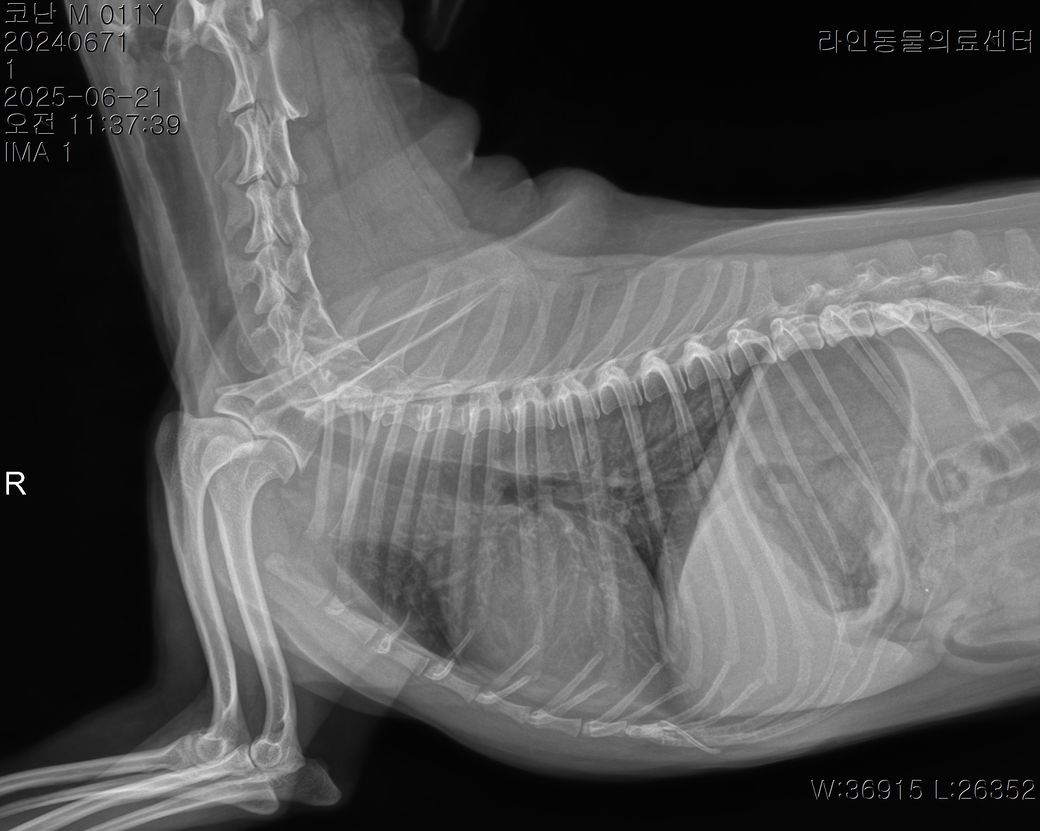

밤에는 멀쩡하다가 오늘 아침부터 애가 갑자기 강아지 혀가 파래지고 복부가 돌처럼 엄청 단단해지고 똥을 싸고 (정상변 5덩어리) 과호흡이 온 경우는 무슨 경우인가요? 애가 안절부절못하면서 집안을 돌아다니면서 혀를내밀고 헥헥거리며 그래서 24시 응급으로 동물병원에선 피검사는 안하고 그냥 엑스레이만 찍었는데 장염이 있다고 하는거같고 변이

안에 있다하는데 별다른 처치를 안하고 돌려보내길래 집에 와서보니 애가 멍해지고 밥을 현재 오후 1시간 이 다되가는데 한끼도 안먹었고 그저 낑낑만 거리고 앉아만있는데 대체 이유가 무엇일까요? 폐는 괜찮다하고 심장병이 있긴한데 심잡음도 별로 안들린다고 그냥 돌려보냈는데 배는 다시 물렁해졌고 헥헥 거림도 신기하게 없어졌고 혀만 약간 보라색빛이 납니다 뭘해야할지도 모르겠고 이게 맞는지도 모르겠습니다

특이사항은 애가 췌장염도 있고 심장병도 있고 장도 안좋고 위에 가스가 찼다고 합니다

그리고 원래 아침부터 밥달라던애가 희한하게 요즘 11시가 되도록 밥을 안찾고 억지로 먹는 그런 느낌도 있고 또 저녁에는 밥을 계속 미친듯이 달라고 또 달라고 짖습니다 그리고 복명음이 들린지 거의 6개월은 넘은거같은데 복명음이 심하게 들립니다 포피염도 있고 노란 고름이 나오며 애가 어느순간부터 실외배변을 고집하고.. 변이나 오줌을 참는 습관이있고 애가 소화력이 약해졌는지 애가 배가 단단해지면 산책을 10분 정도 시켜주면 배가 다시 물렁해집니다 헌재는 허리디스크 때문에 가바펜틴과 엔세이드 근이완제를 먹이고 있고 허리디스크 때문에 산책은 전혀 안해주고 있으며 엑스레이상 가스와 변이 있는 상태인데(아침에 5덩어리의 변을 누었음에도) 왜 이렇게 소화기가 문제인지를 도무지 이유를 모르겠습니다 11살 토이푸들입니다 그리고 식이알러지 증상도 있습니다 (한쪽 턱을 긁는다던지, 귀를 긁는다던지 발을 빤다던지 하는 증상) 마지막으로 애가 밤만되면 꼭 이불을 이유없이 하루 종일 빨아서 이불이 항상 침으로 범벅이 되있습니다 (이것도 거의 근 반년은 된거같습니다) 어제 밤은 입맛을 살짝 쩝쩝 다셨으나 별 다른 증상은 없었습니다 병원에 가도 하는건 없고 그냥 산소방에 넣어두고 엑스레이찍고 청진하고 이게 다인제 이게 맞는 처치인지도 모르겠고 약 하나 주사하나 뭐 하나 조치가 취해진게 아무것도 없는 상황입니다 제발 예측이 되는 질병들이 있으면 알려주세요 심잡음은 약하게 들린다하여 b1 같다고 합니다 그리고 포피에는 노란 농이 나오고 있고 만지려고 하면 엄청 신경질적으로 변하는데 이 경우 장도 저렇게 안좋은데 포피염 항생제를 처방받아야할지 이것도 감도 안옵니다.